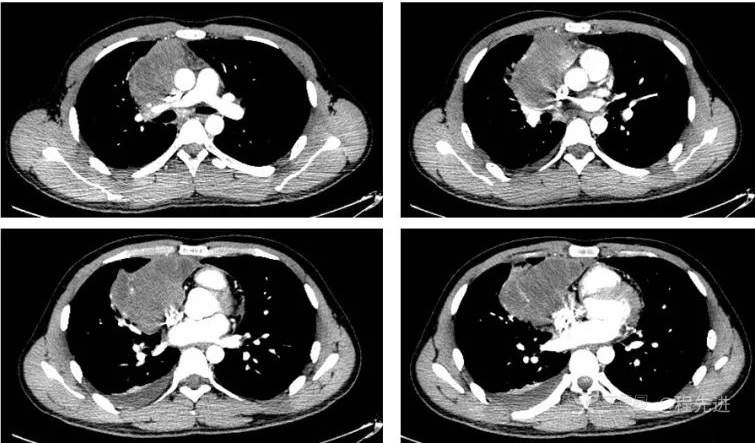

CT增强